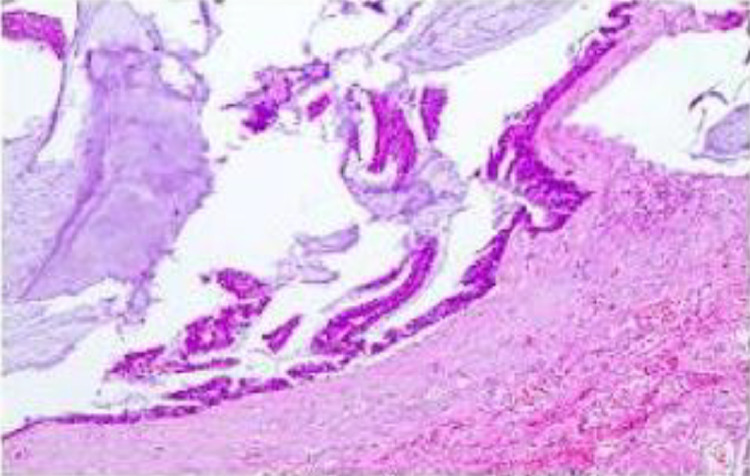

Fig. 3.

Histological findings from a biopsy performed in 2023 demonstrating significant mucinous adhesion within the pathological specimen. Visible within the mucus were mucinous cells, some of which form fine papillary structures with basally located rod-shaped nuclei. These features were indicative of low-grade pseudomyxoma peritonei.

A 62-year-old male with no prior history of tumors presented with unexplained epigastric pain and intermittent episodes of abdominal distension lasting more than 8 years. Initially admitted to our hospital in 2015, he underwent no specific treatment during that visit. Subsequent diagnostic efforts included a computed tomography (CT) scan of the abdomen and pelvis with contrast, revealing multiple low-density masses encircling the liver and spleen, as well as within the greater and lesser omentum (Fig. 1). The patient underwent surgical excision of the identified masses in other hospitals in 2015 and again in 2018. In 2023, the patient returned to our hospital, where a repeat CT scan of the abdomen and pelvis with contrast disclosed diffuse low-density masses surrounding the liver, spleen, greater and lesser omentum, mesentery, and pelvic cavity, with scattered calcifications and slight enhancement upon contrast administration. The imaging revealed deformation of the liver and spleen due to pressure, evidenced by hepatic and splenic scalloping. Additionally, multiple low-density cystic lesions with partial marginal calcification were observed in both liver and spleen. Compression of the gastrointestinal tract, pancreas, and bladder was notably apparent (Fig. 2). Surgical "resection of peritoneal and retroperitoneal lesions" was subsequently performed at our hospital. The surgical findings suggested an appendiceal myxoma origin. Histopathological examination using light microscopy identified extensive mucin adhesion within the pathological tissue, with visible mucinous cells, some exhibiting fine papillary structures and basally located rod-shaped nuclei (Fig. 3). Immunohistochemical staining yielded the following results: Ki-67 (+, about5%), MLH1 (+), MSH2 (+), MSH6 (+), P53 (+), PMS2 (+). Based on these findings, the patient was diagnosed with low-grade pseudomyxoma peritonei.